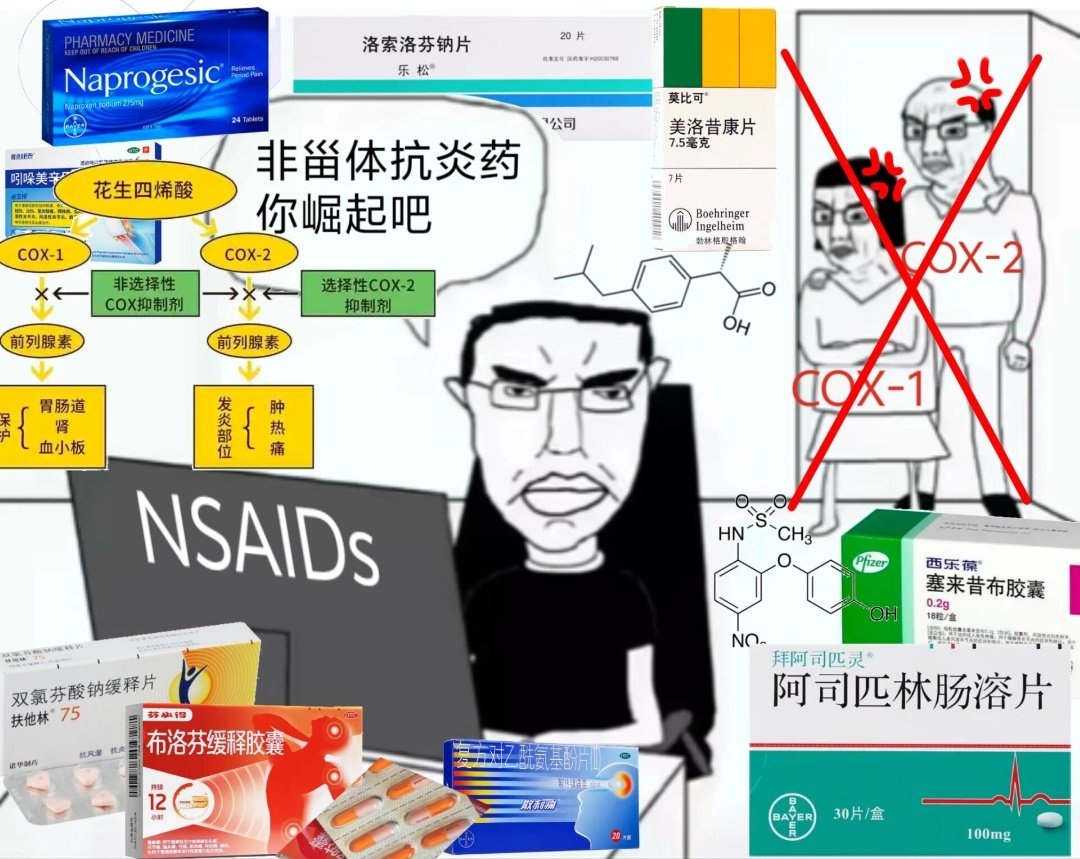

由于我现在快(痛经)痛死了,有感而发简单说说止痛药

常见NSAIDs先稍稍,首选塞来昔布,0.5-1h起效,对肠胃刺激小可以空腹服用,有中上的镇痛强度和中短的持续时间

那么有没有更强的呢🥹有,依托考昔,起效要1h以后,有着22h的长半衰期所以管一整天没什么问题,同样对胃刺激小适合我这种快痛晕过去了直接抓来吃

双氯芬酸钾起效也快适合空腹,但如果胃没那么好就可以一整个分不清哪里在痛了,所以还是垫点食物会比较好

那么再推荐一个双氯芬酸的直肠栓剂版本,直接绕过消化道刺激这关并且起效很快!